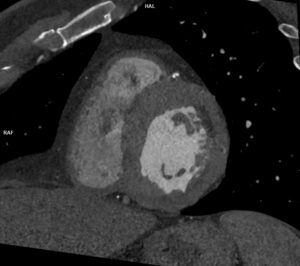

Discuţie caz nr 66:

Pacientul este scanat imediat posttraumatic în momentul zero și se pune în evidență creștere de volum a ligamentului încrucișat posterior în jumătatea distală cu întrerupere completă a continuității fibrilelor; deasemenea, se observă avulsie proximală a ligamentului colateral medial împreună cu un mic fragment osos din condilul femural intern.

Pacientul a fost scanat apoi la 2 luni posttraumatic și la un an posttraumatic și imaginile atașate sunt utile pentru a observa evoluția acestor leziuni.

Examinarea IRM este indicată pentru diagnosticul inițial împreună cu examenul clinic al medicului ortoped. Este foarte utilă în evidențierea leziunilor meniscale, ligamentare sau osteocondrale și pentru urmărirea lor în dinamică.